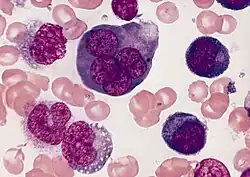

Hematopathology

Hematopathology is the study of diseases of blood cells (including constituents such as white blood cells, red blood cells, and platelets) and the tissues, and organs comprising the hematopoietic system. The term hematopoietic system refers to tissues and organs that produce and/or primarily host hematopoietic cells and includes bone marrow, the lymph nodes, thymus, spleen, and other lymphoid tissues. In the United States, hematopathology is a board certified subspecialty (licensed under the American Board of Pathology) practiced by those physicians who have completed a general pathology residency (anatomic, clinical, or combined) and an additional year of fellowship training in hematology. The hematopathologist reviews biopsies of lymph nodes, bone marrows and other tissues involved by an infiltrate of cells of the hematopoietic system. In addition, the hematopathologist may be in charge of flow cytometric and/or molecular hematopathology studies.